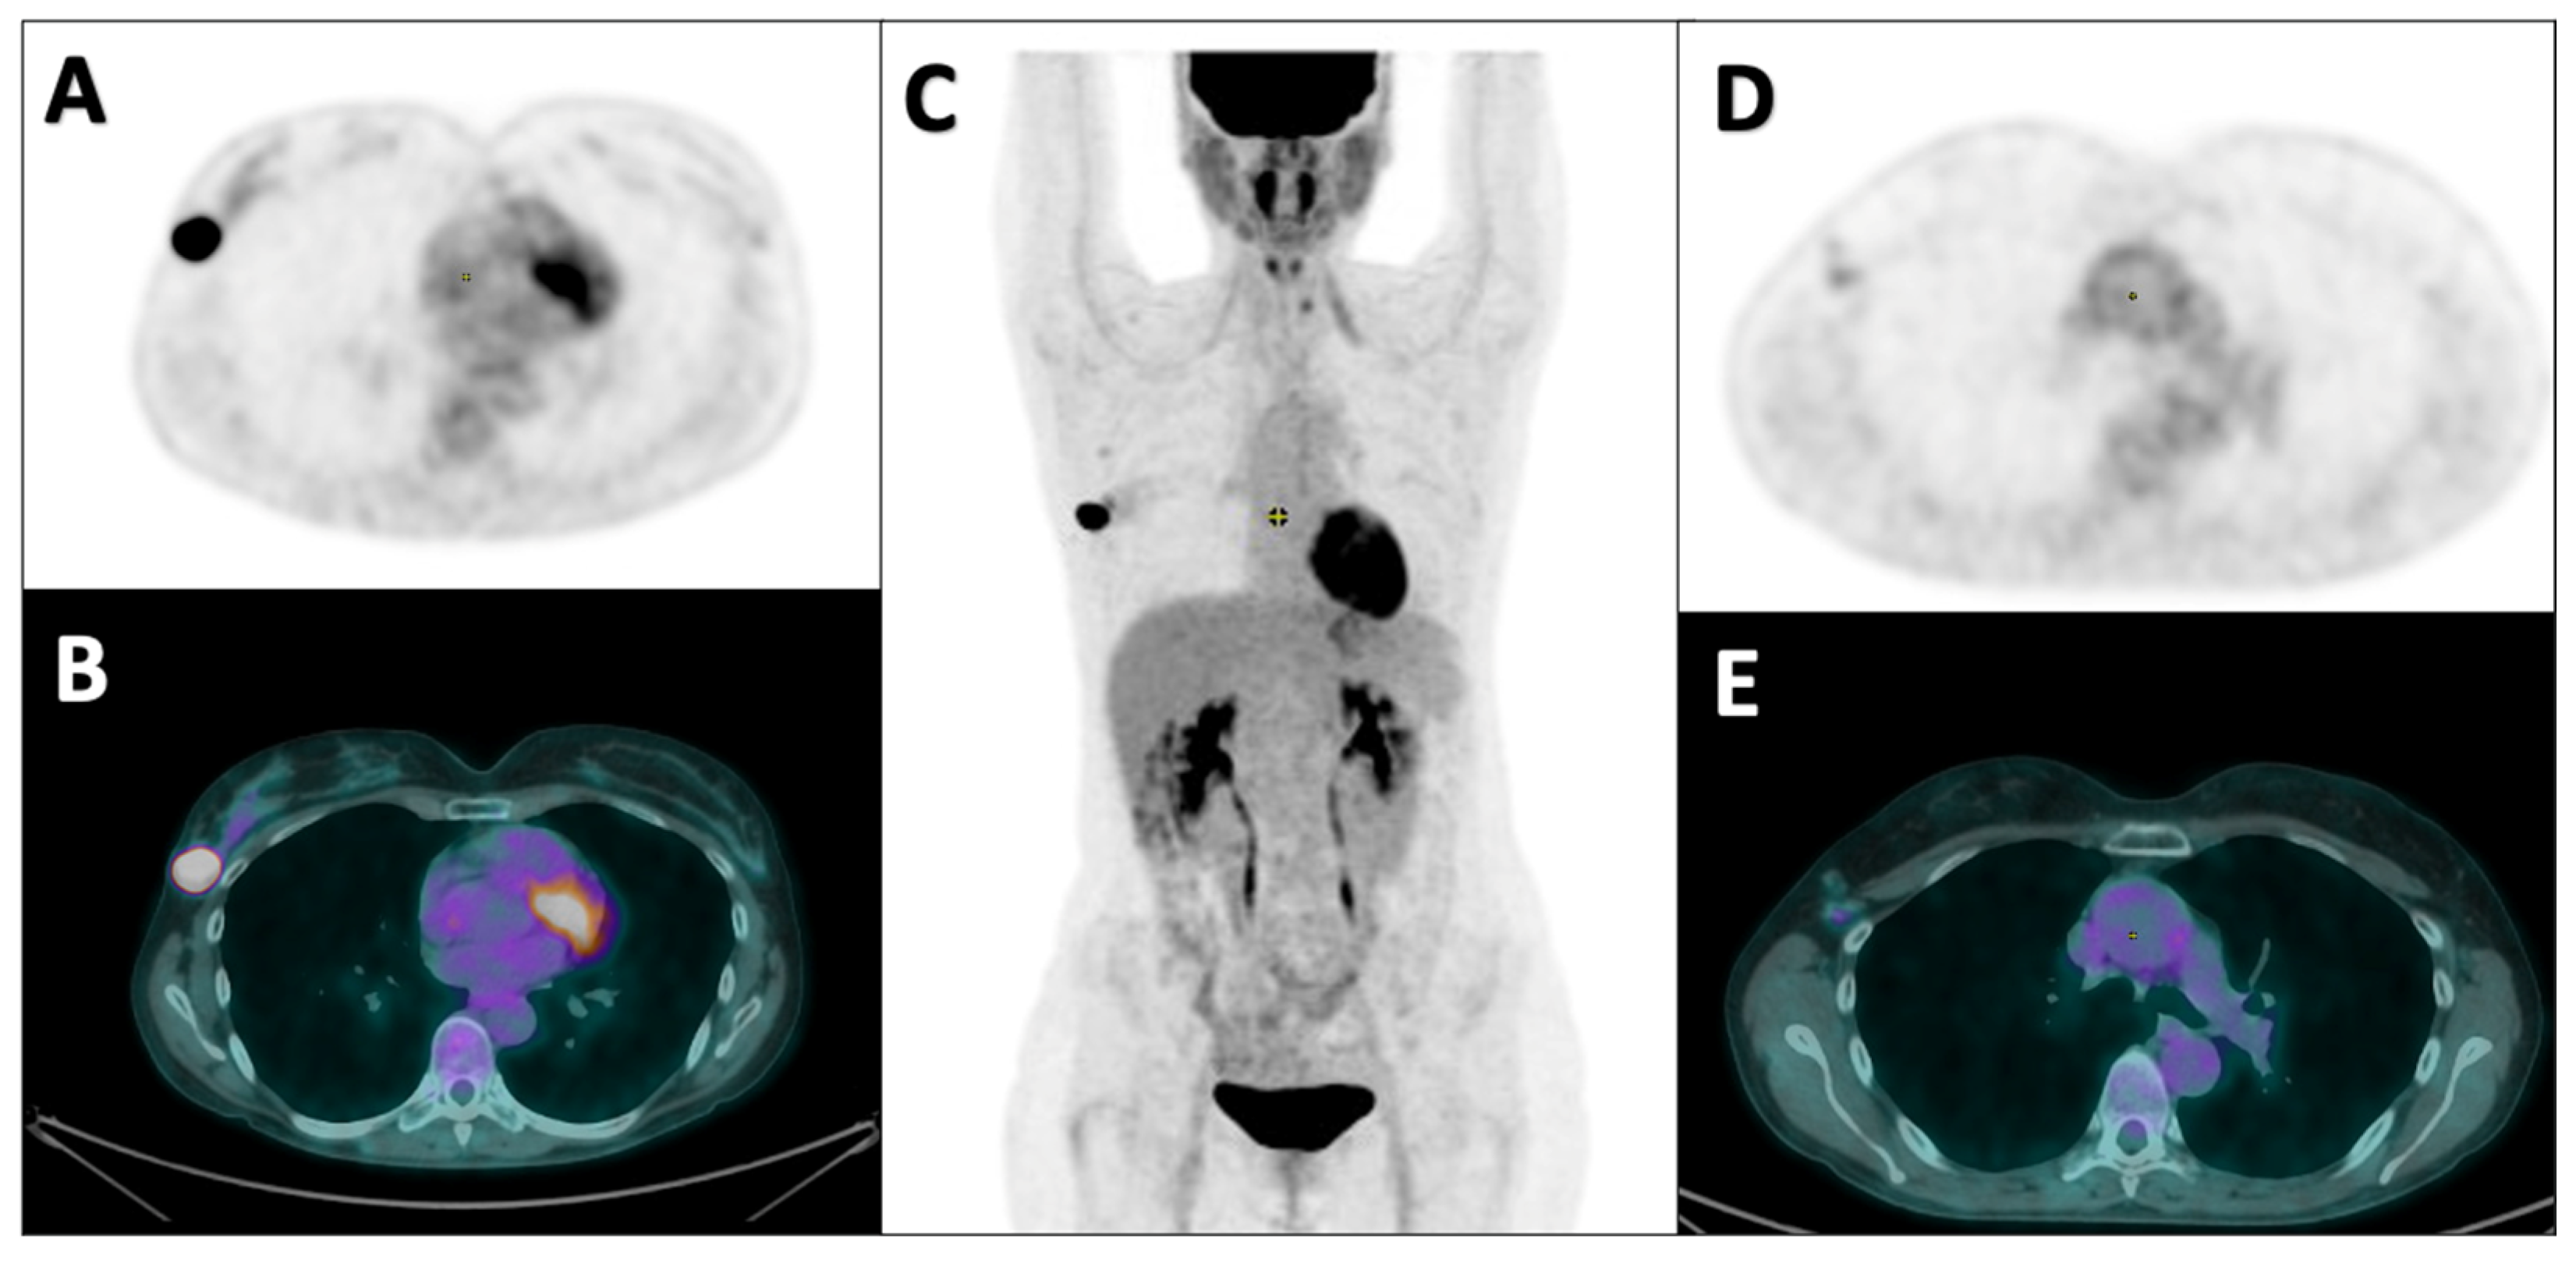

2.2. PET Acquisition and Image Analyses